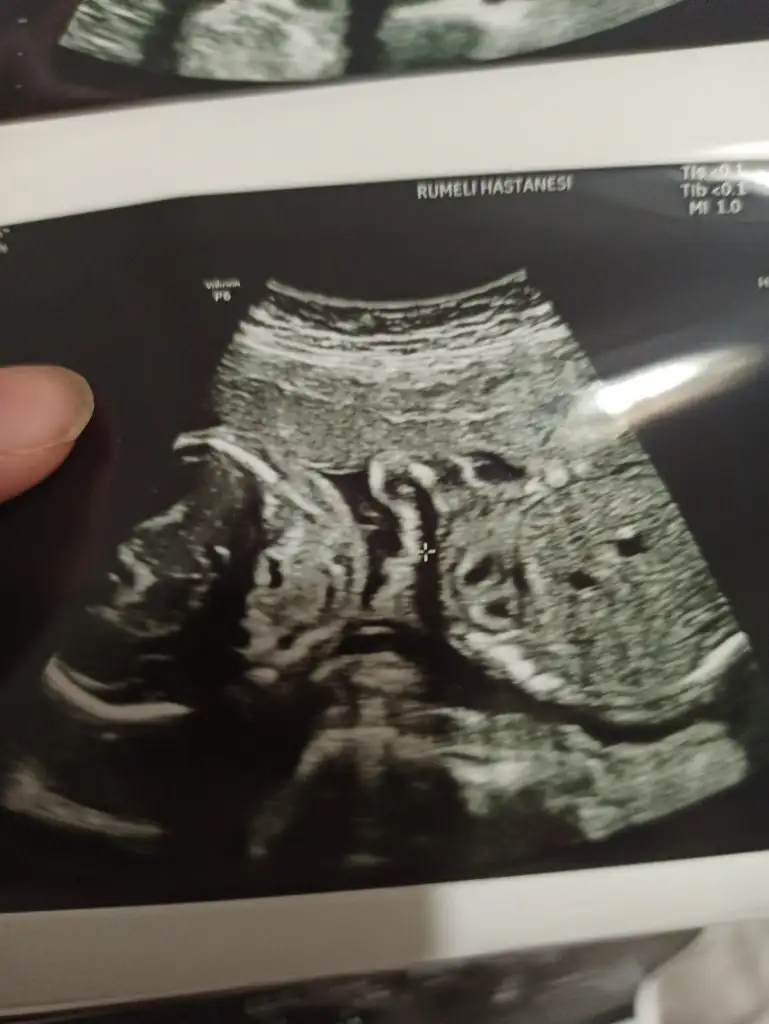

Kız bence. Ama tabiki her şeyin hayırlısı olsun. Şimdi koz diye kodlama. İllaki öğreneceksin.Burda 14 hafta 6gunluk du 92.2m ölçtü yer

Sağlıkla gelsinBugün ki ultrason fotoğrafı